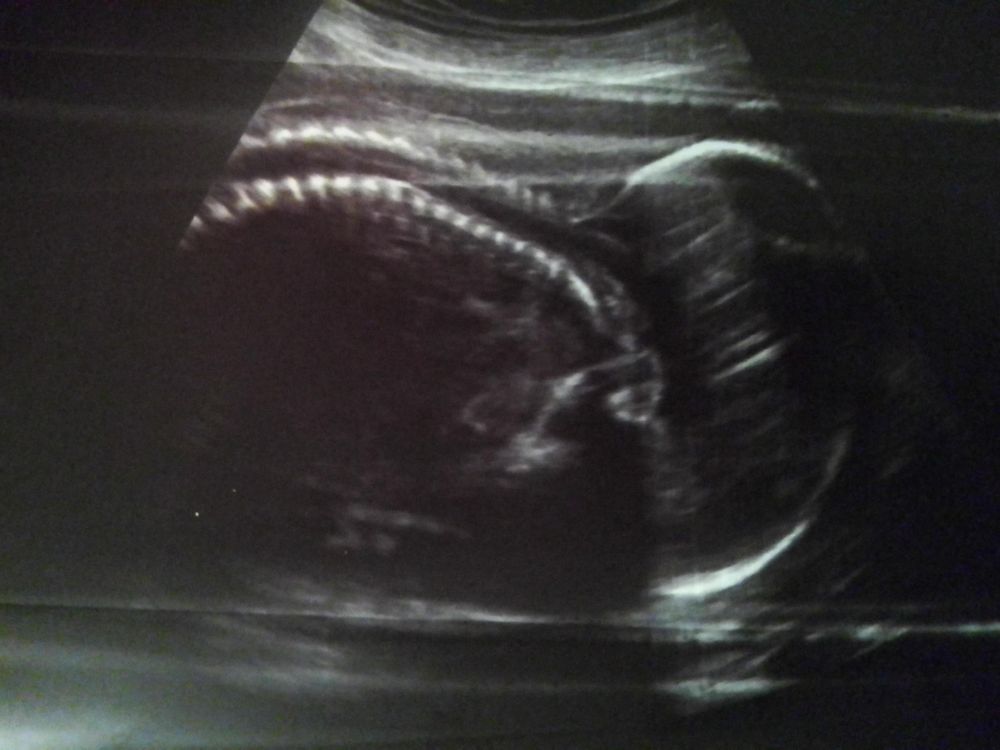

ниже прикреплю снимки абсолютно «нормальных» спинок😌 специально сохранила примерно в таком же положении как у Вас